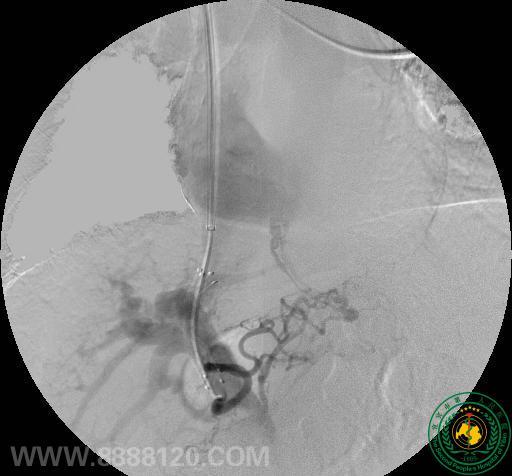

2012年11月15日,放射介入科成功开展了一例经颈静脉肝内门体支架分流术(TIPS),这是宜宾市第一例经颈静脉肝内门体支架分流术(TIPS)。

患者为60岁老年男性,诊断肝硬化,反复腹胀,顽固性腹水。经消化科陈扬主任医师、介入科曹跃勇主任医生、朱军主治医生及黄勇医师反复研究病情,决定对其实施TIPS手术。术中经肝右静脉成功穿刺门静脉右支,并顺利行分流道球囊扩张,再于适当位置释放覆膜支架一枚。术后造影见门静脉内血流经分流道进入肝静脉,并由下腔静脉回到右心房。术中及术后患者未见特殊不适。